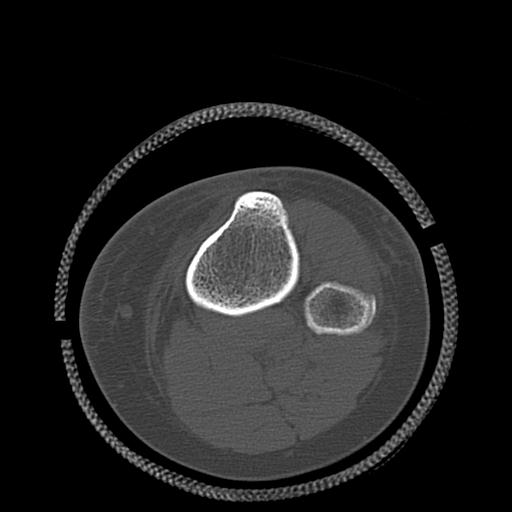

56476 8/28 4R 1/21 2R 左足関節 デジカメ写真 72歳女性 右足関節AS